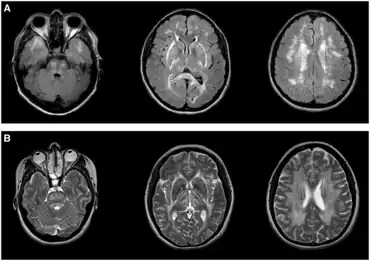

| Leukoencephalopathies in adults-a) Typical imaging appearance of CADASIL b) CARASAL | |